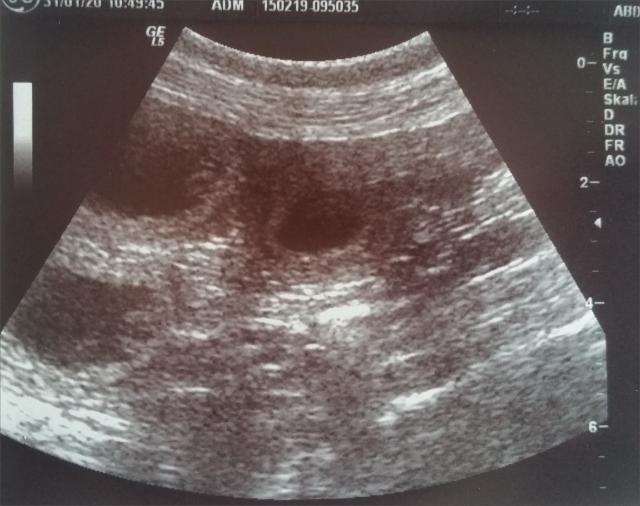

31.01.2020: Wir waren heute beim Ultraschall mit Gina

und haben kleine Babys im Bauch gesehen! :-)

Somit erwarten wir unseren A2-Wurf Anfang März! Bei

Interesse bitte melden! :-)